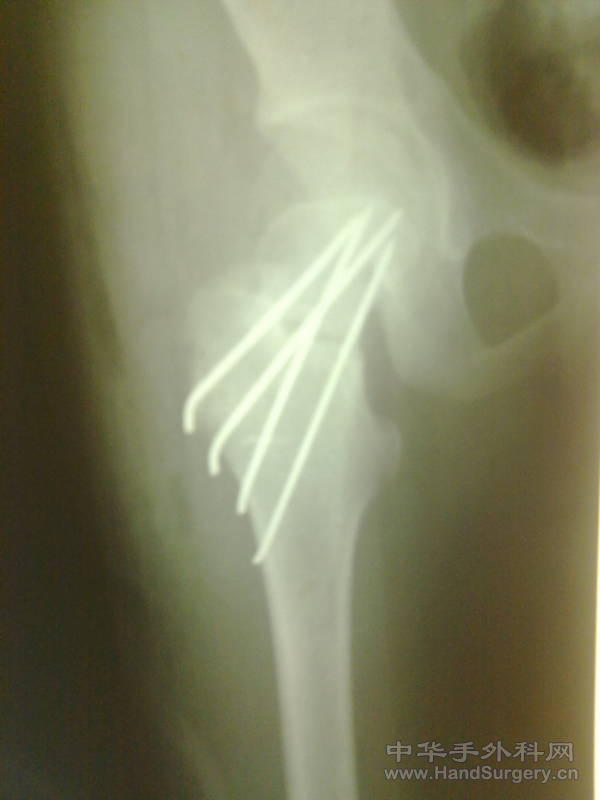

发一例股骨颈骨折

患者17岁,外伤致股骨颈骨折,请大家看看是否有更好的固定方法。

为什么用克氏针而不用空心螺钉啊?

股骨颈骨折用克氏针内固定,真是第一次见到.唉?

原则上是应该行空心钉内固定,估计作者想减少对骺板得损伤吧。

用克氏针固定股骨颈,患者术后要卧床多久啊!经典固定方法,强人!用克氏针,竟然用克氏针。。。。。。。。。

年青人,如为这种骨折很多是高能量损伤,坏死率比老人更大,再加上这种处理,我想也就差不多了,这伤还是按原则来吧,三枚双头空心加压,呈品字固定。术后尽量晚负重。

用空心钉的损伤是否会比这个大的多,更容易造成股骨头的坏死。